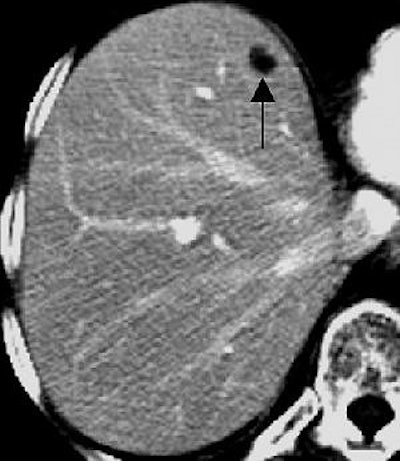

| Transverse contrast-enhanced helical CT scans of the abdomen in a 70-year-old woman with infiltrating ductal carcinoma (stage IIA at initial presentation) and hepatic cysts. Above, baseline scan obtained with 7-mm-thick sections shows a hepatic lesion (arrow) deemed TSTC. Below, follow-up scan obtained with 7.5-mm-thick sections 11 months later shows that the hepatic lesion (arrow) has increased in size -- from 17 x 10 mm to 20 x 10 mm. A second hepatic lesion (not shown) showed a similar increase in size -- from 3 x 3 mm to 5 x 5 mm. Subsequent MR imaging of the abdomen revealed the presence of hepatic cysts, but no hepatic metastasis. Figure 3AB, Hanan KI, Patterson SA, Panicek DM, "Hepatic Lesions Deemed Too Small to Characterize at CT: Prevalence and Importance in Women with Breast Cancer," Radiology 2005; 235:872-878. |